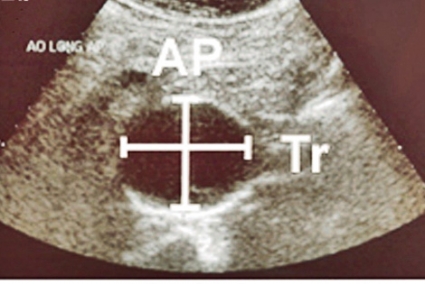

Ultraljudsundersökningen vid screening (Figur 2) skiljer sig från en fullvärdig aortaundersökning såtillvida att dess primära syfte är att med hög säkerhet utesluta sjukdom. Vid screening läggs transduktorn i kärlets längsriktning (Figur 2 a) och maximal infrarenal anteroposterior diameter mäts enligt principen »leading edge to leading edge« (Figur 3). Måttet anges på ett protokoll, som också innehåller uppgifter om eventuella visibilitetsproblem samt undersökarens initialer. Vid diameter ≥25 mm anges också diametern med transduktorn vinkelrätt mot kärlet (Figur 2 b).